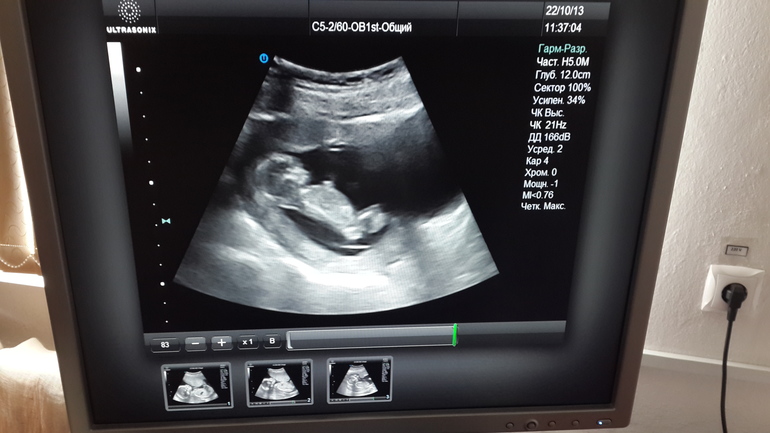

Узи первого триместра форум

Узи первого триместра форум 117 фото